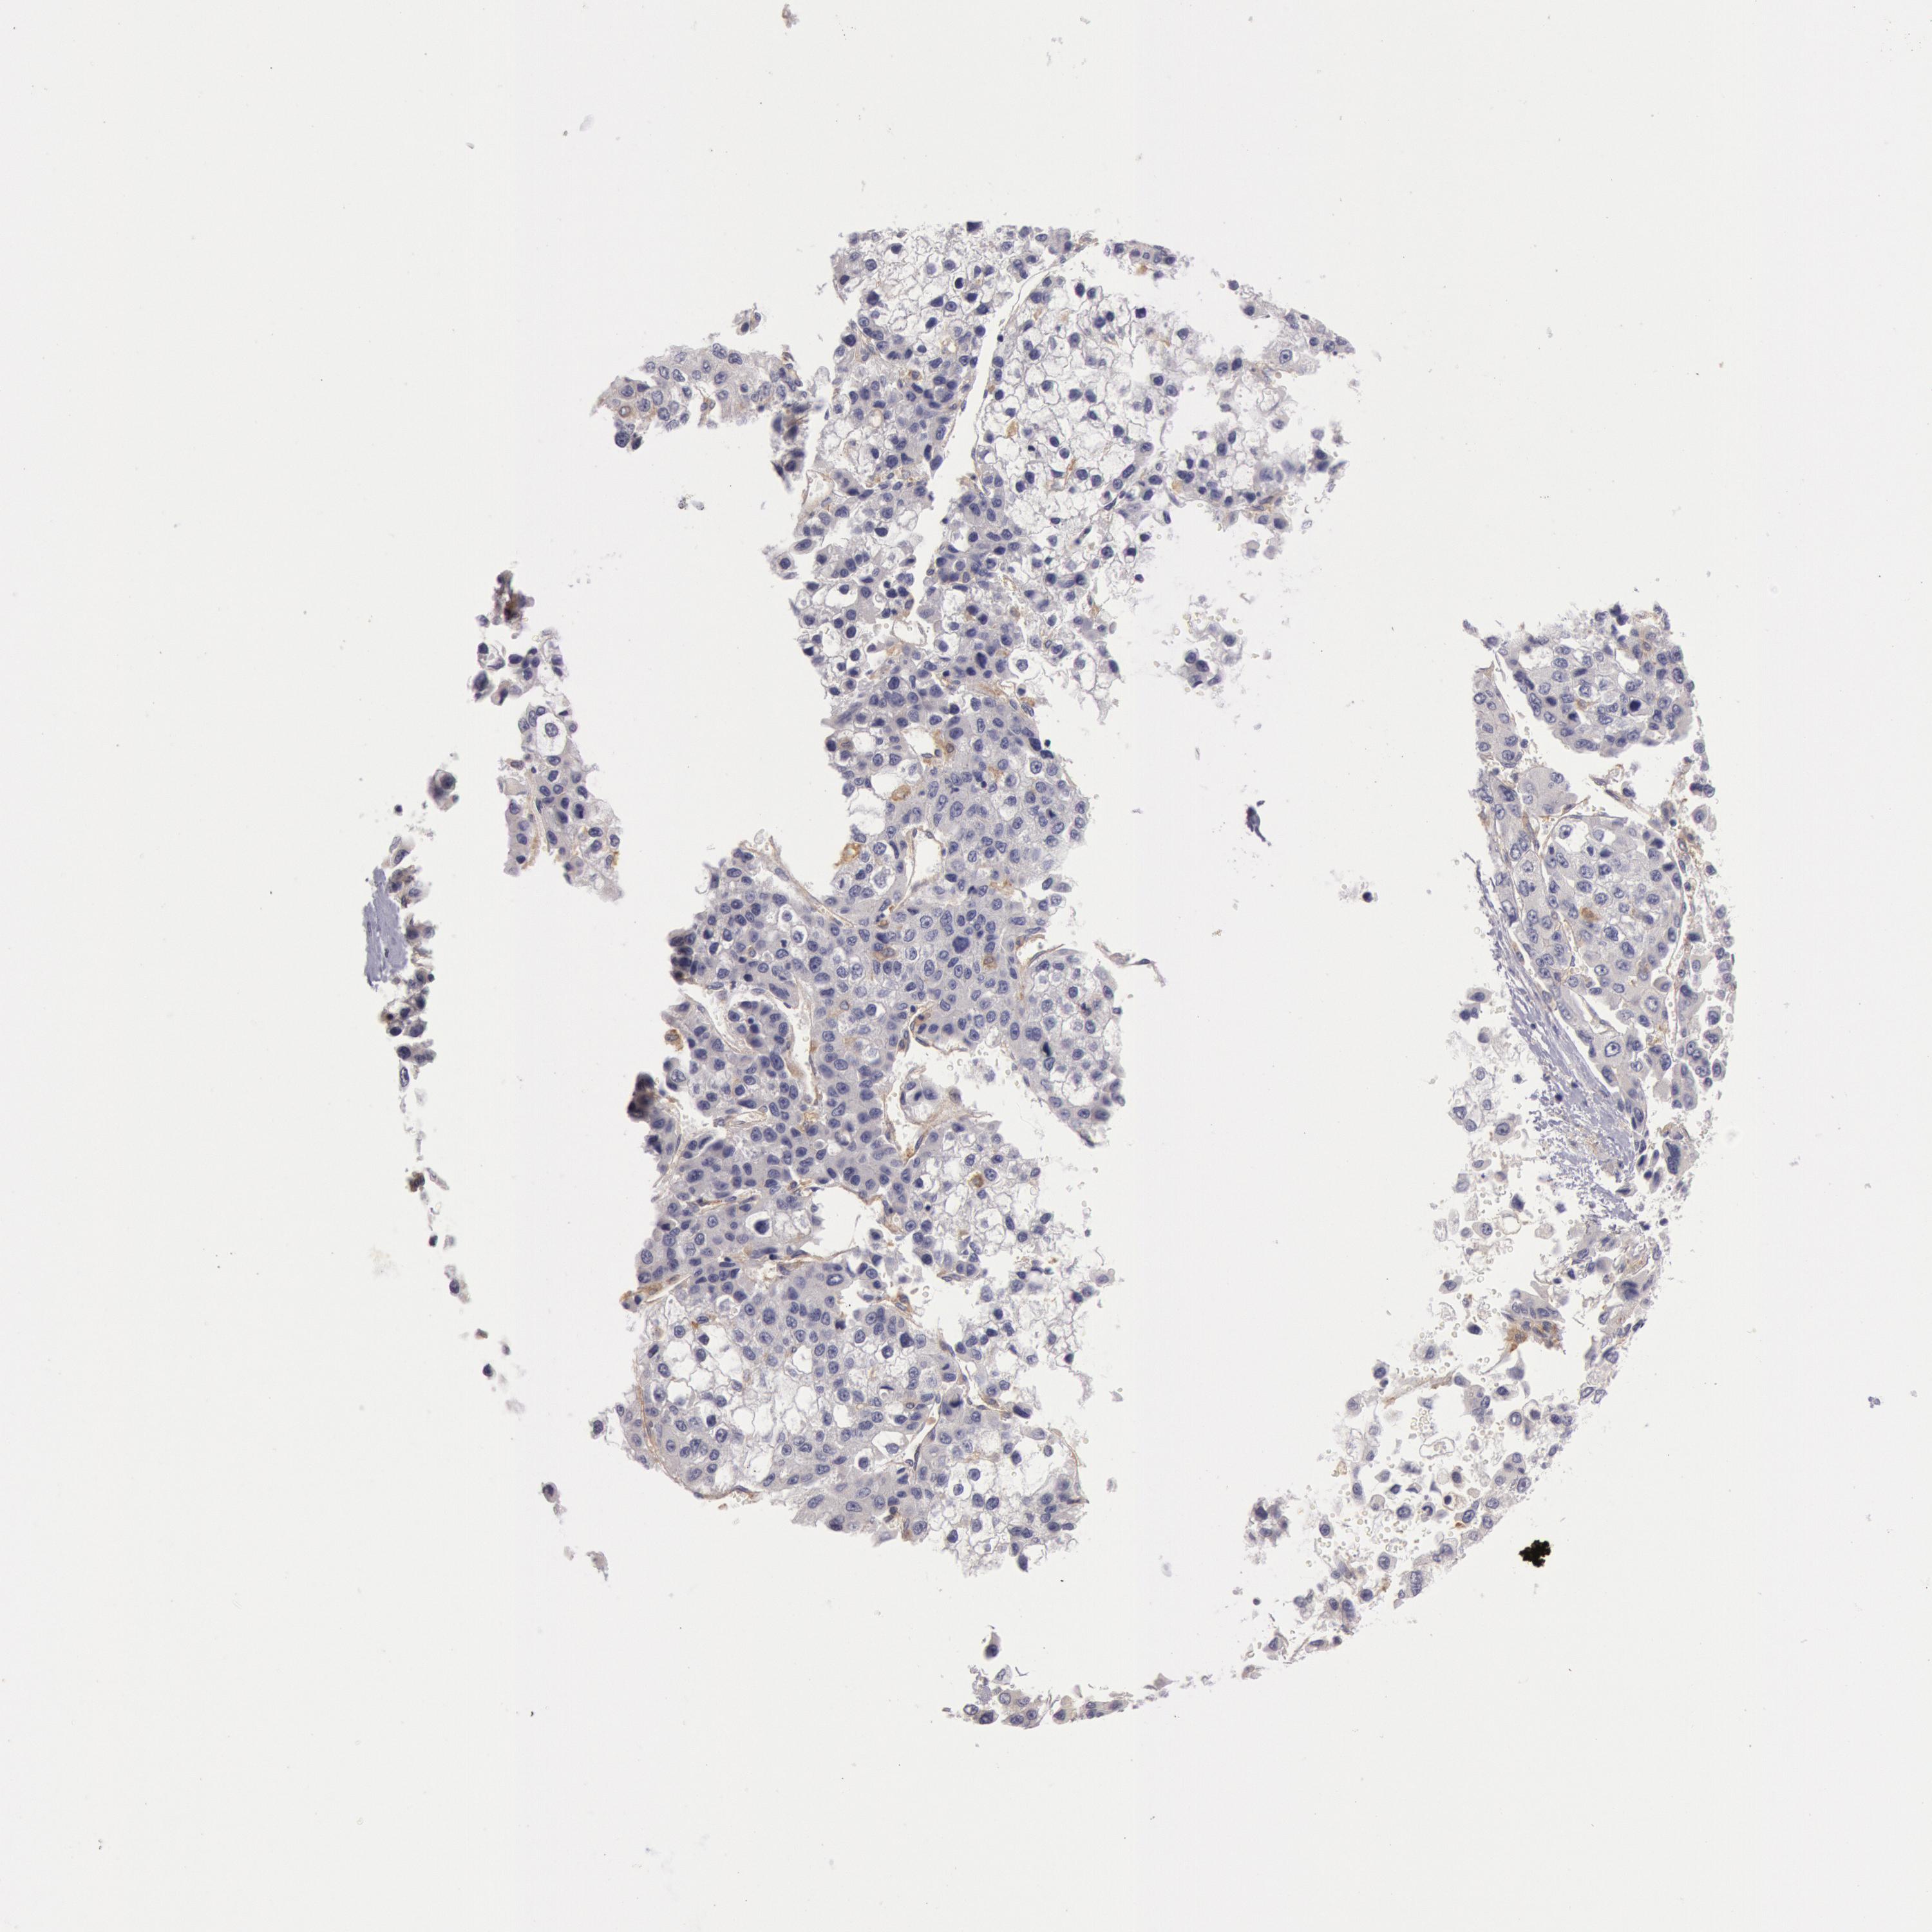

LIVER CANCER - Protein expressioni

A mouse-over function shows sample information and annotation data. Click on an image to view it in a full screen mode. Samples can be filtered based on level of antibody staining by selecting one or several of the following categories: high, medium, low and not detected. The assay and annotation is described here.

Antibody stainingi

Antibody staining in the annotated cell types in the current human tissue is reported as not detected, low, medium, or high, based on conventional immunohistochemistry profiling in selected tissues. This score is based on the combination of the staining intensity and fraction of stained cells.

Each image is clickable and will lead to virtual microscopy that enables deeper exploration of all samples and also displays staining intensity scores, fraction scores and subcellular localization as well as patient and tissue information for each sample.

Antibody HPA001356

Staining

High

Medium

Low

Not detected

Intensity

Strong

Moderate

Weak

Negative

Quantity

>75%

75%-25%

<25%

None

Location

Nuclear

Cytoplasmic/membranous

Cytoplasmic/membranous,nuclear

Carcinoma, Hepatocellular, NOS